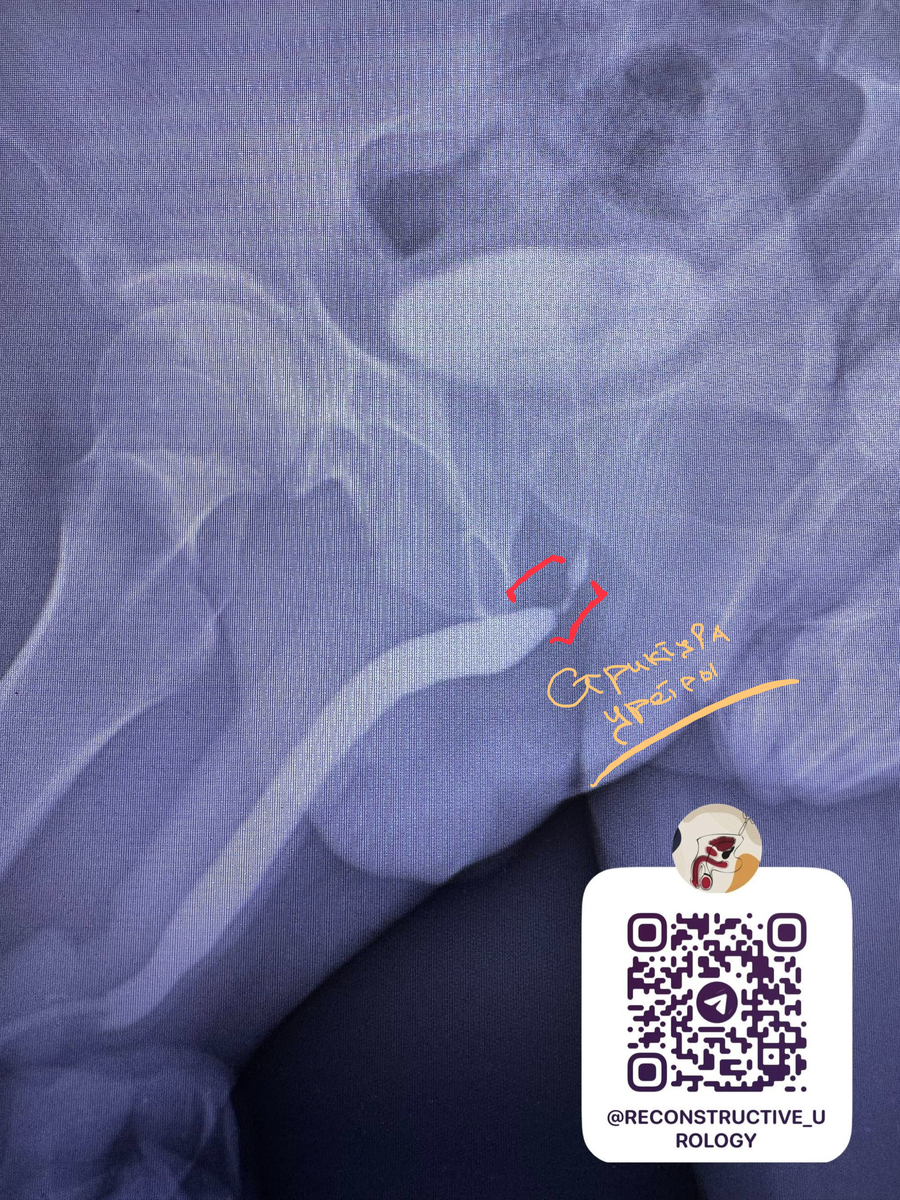

Стриктура бульбозного отдела уретры после катетеризация мочевого пузыря

• Ретроградная уретрография: Выявлено критическое сужение до 1,5 мм на протяжении 15 ммв проксимальном бульбозном отделе уретры

Основной диагноз: Стриктура проксимального бульбозного отдела уретры.

Хирургическая тактика: Анастомотическая пластика уретры «конец в конец».